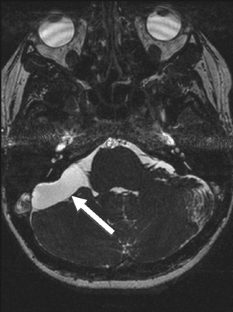

Cerebellopontine angle arachnoid cyst containing ectopic choroid plexus—case report

We present a rare and interesting case of a cerebellopontine angle cyst containing ectopic choroid plexus tissue in a 26 year-old female. Surgical resection was performed, and histological examination confirmed the presence of choroid plexus in the cyst wall. This is the first reported case of ectopic choroid plexus at the cerebellopontine angle in an adult. We present the case and review the literature.

Fig. 1